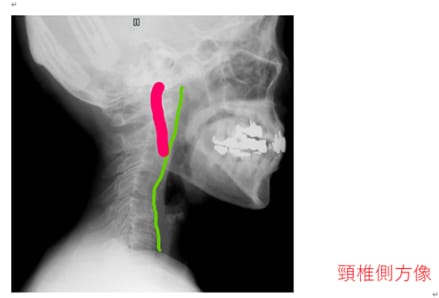

頚椎を横から撮影したレントゲンです。

こちらもラインを引いてみました。

理想の頚椎の並びは、

のど仏の方にせり出るようなカーブを描きます。

ストレートネックというより、

逆カーブを描いていますね。

こうなると

約5kgある頭蓋の重さが直接肩で支えることになるので、

肩も凝ります。

そして、見逃してはならないのが、

ピンクで色を付けた頸動脈が

レントゲンで白く写っていることです。

血管の石灰化が起きていることを表しています。

脳への血流が乏しくなって、良いことはありません。

認知症の原因になりえますし、

脳梗塞の原因にもなります。

(石灰化脳梗塞は脳梗塞の全体の5~6%。

石灰化に伴って出来るプラークによる脳梗塞は

また、頸動脈でこれほどの石灰化が

起きているということは、

他の血管でも石灰化が起きている可能性も

否定できないですよね。